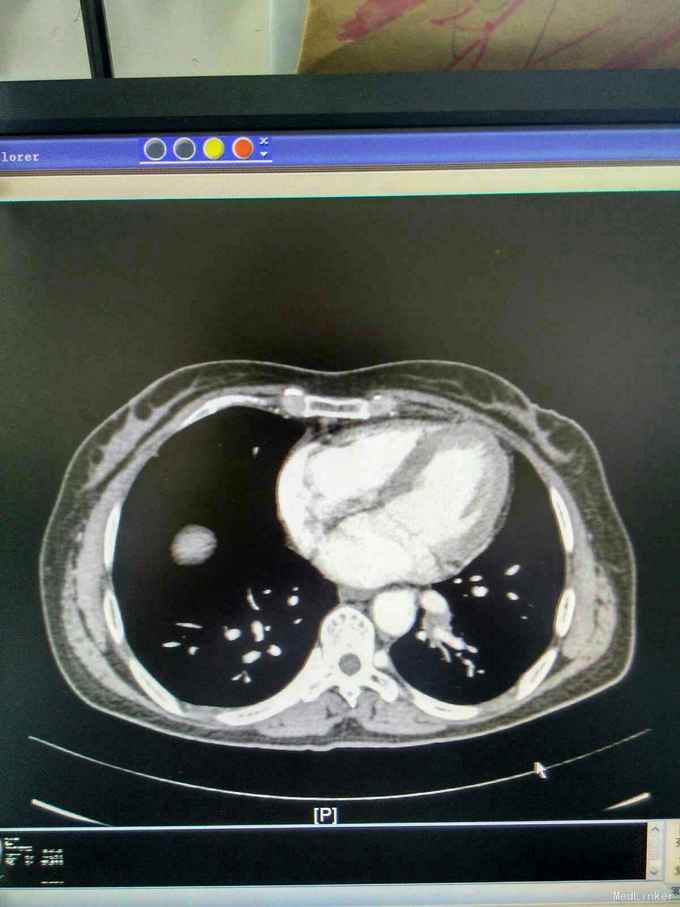

我院胸部ct增强,见左下肺病灶内见一异常供血血管,发自降主动脉,病灶周围见斑片状磨玻璃影。诊断为左肺下叶肺隔离症,转外科治疗。

患者外院胸部ct提示左下肺块影,原计划行ct引导下肺穿次活检术,我院胸部ct增强后发现,病灶为肺隔离症。遂转外科行左下肺切除术。